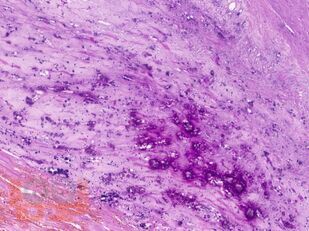

Учебное пособие разработано по дисциплине «Патологическая анатомия - патологическая анатомия головы и шеи» в соответствии с Федеральным государственным образовательным стандартом высшего профессионального образования для студентов, обучающихся по основным образовательным программам высшего образования - программам специалитета по специальности «Стоматология».

В учебном пособии представлен теоретический материал, перечень макропрепаратов и микропрепаратов, демонстрирующих типовые проявления патологических процессов. В цветных иллюстрациях и в описании микропрепаратов сделан акцент на наиболее важных гистологических изменениях, позволяющих на светооптическом уровне диагностировать и дифференцировать состояния, отклоняющиеся от нормы, в том числе с использованием различных гистологических окрасок. Пособие помогает выделить главные аспекты изучаемых патологических процессов, организовать и конкретизировать учебный процесс.